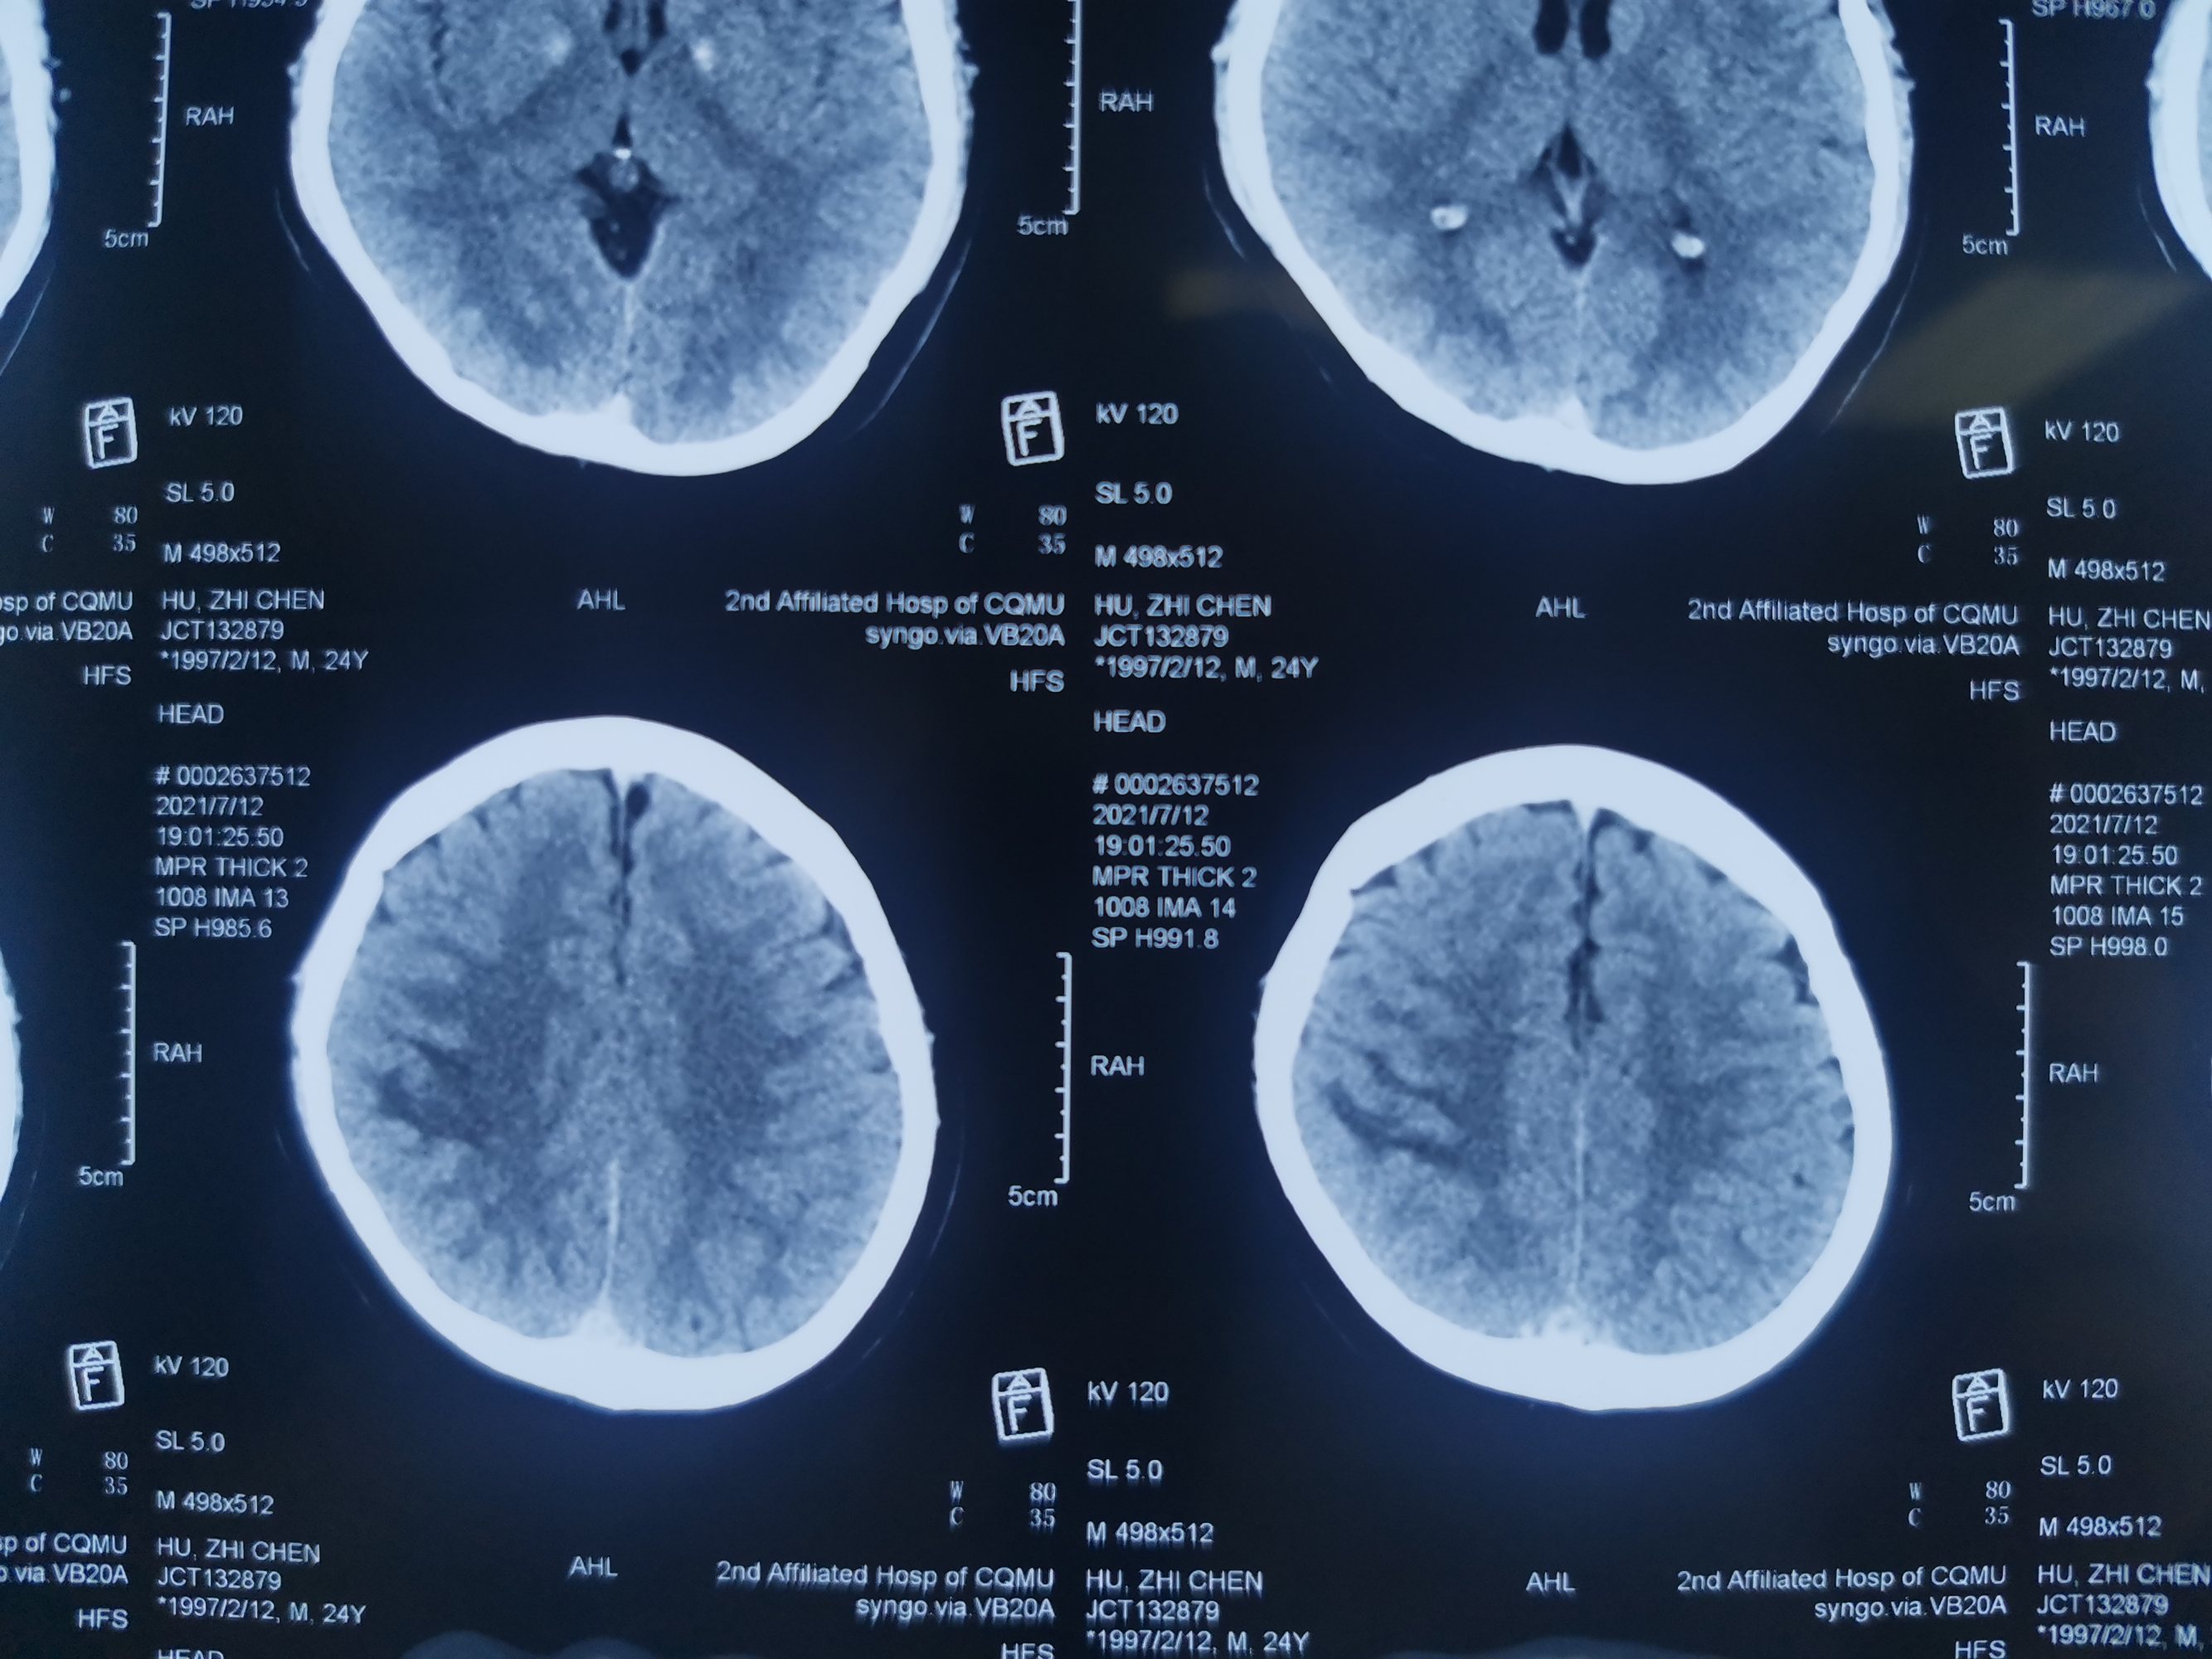

外院CT混杂低密度信号

外院磁共振增强见,矢状窦局部充盈缺损。

增强显示矢状窦长节段充盈缺损,D-2聚体大于正常上限5倍以上。我科诊断考虑上矢状窦血栓形成伴多发多次脑梗死伴出血。

矢状窦全程血栓,与外院相比血栓明显扩大。立即急诊行脑血管造影+介入取栓术。